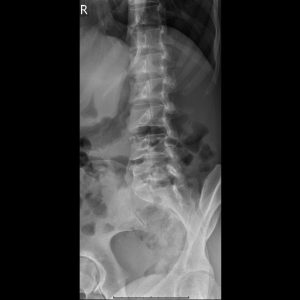

L-spine Lateral view